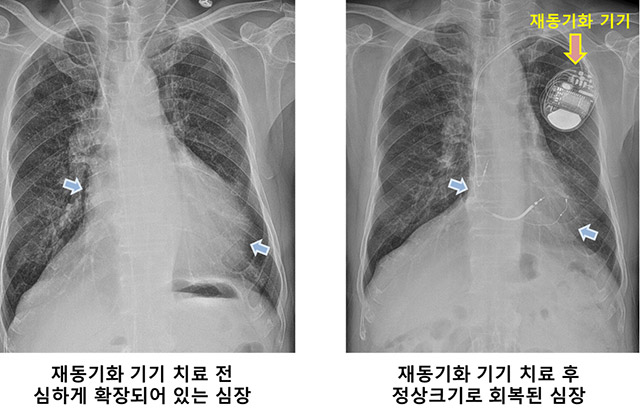

삼성서울병원 심장뇌혈관병원 부정맥센터는 국내에서 처음으로 심장재동기화치료 300예를 달성했다고 밝혔다.

심장재동기화치료란 좌심실로 가는 전기 신호가 느려지면서 엇박자로 뛰는 심장 박동을 바로 잡는 치료다. 심장이 비대칭적으로 수축하면 심장이 붓고 숨이 차는 심부전이 생기는데, 약물 치료에도 별다른 효과가 없으면서 비대칭적인 심장수축을 보이는 만성 심부전 환자가 심장재동기화치료의 주 대상이다.

시술이 어렵지만, 치료 효과는 극적이다. 심장 기능이 100점 만점 기준으로 50 ~ 60점에 불과하던 환자들이 치료를 받고 나면 70 ~ 80%는 호전된다고 알려져 있다. 이 가운데 3분의 1은 거의 정상 수준에 가까워지기도 한다.